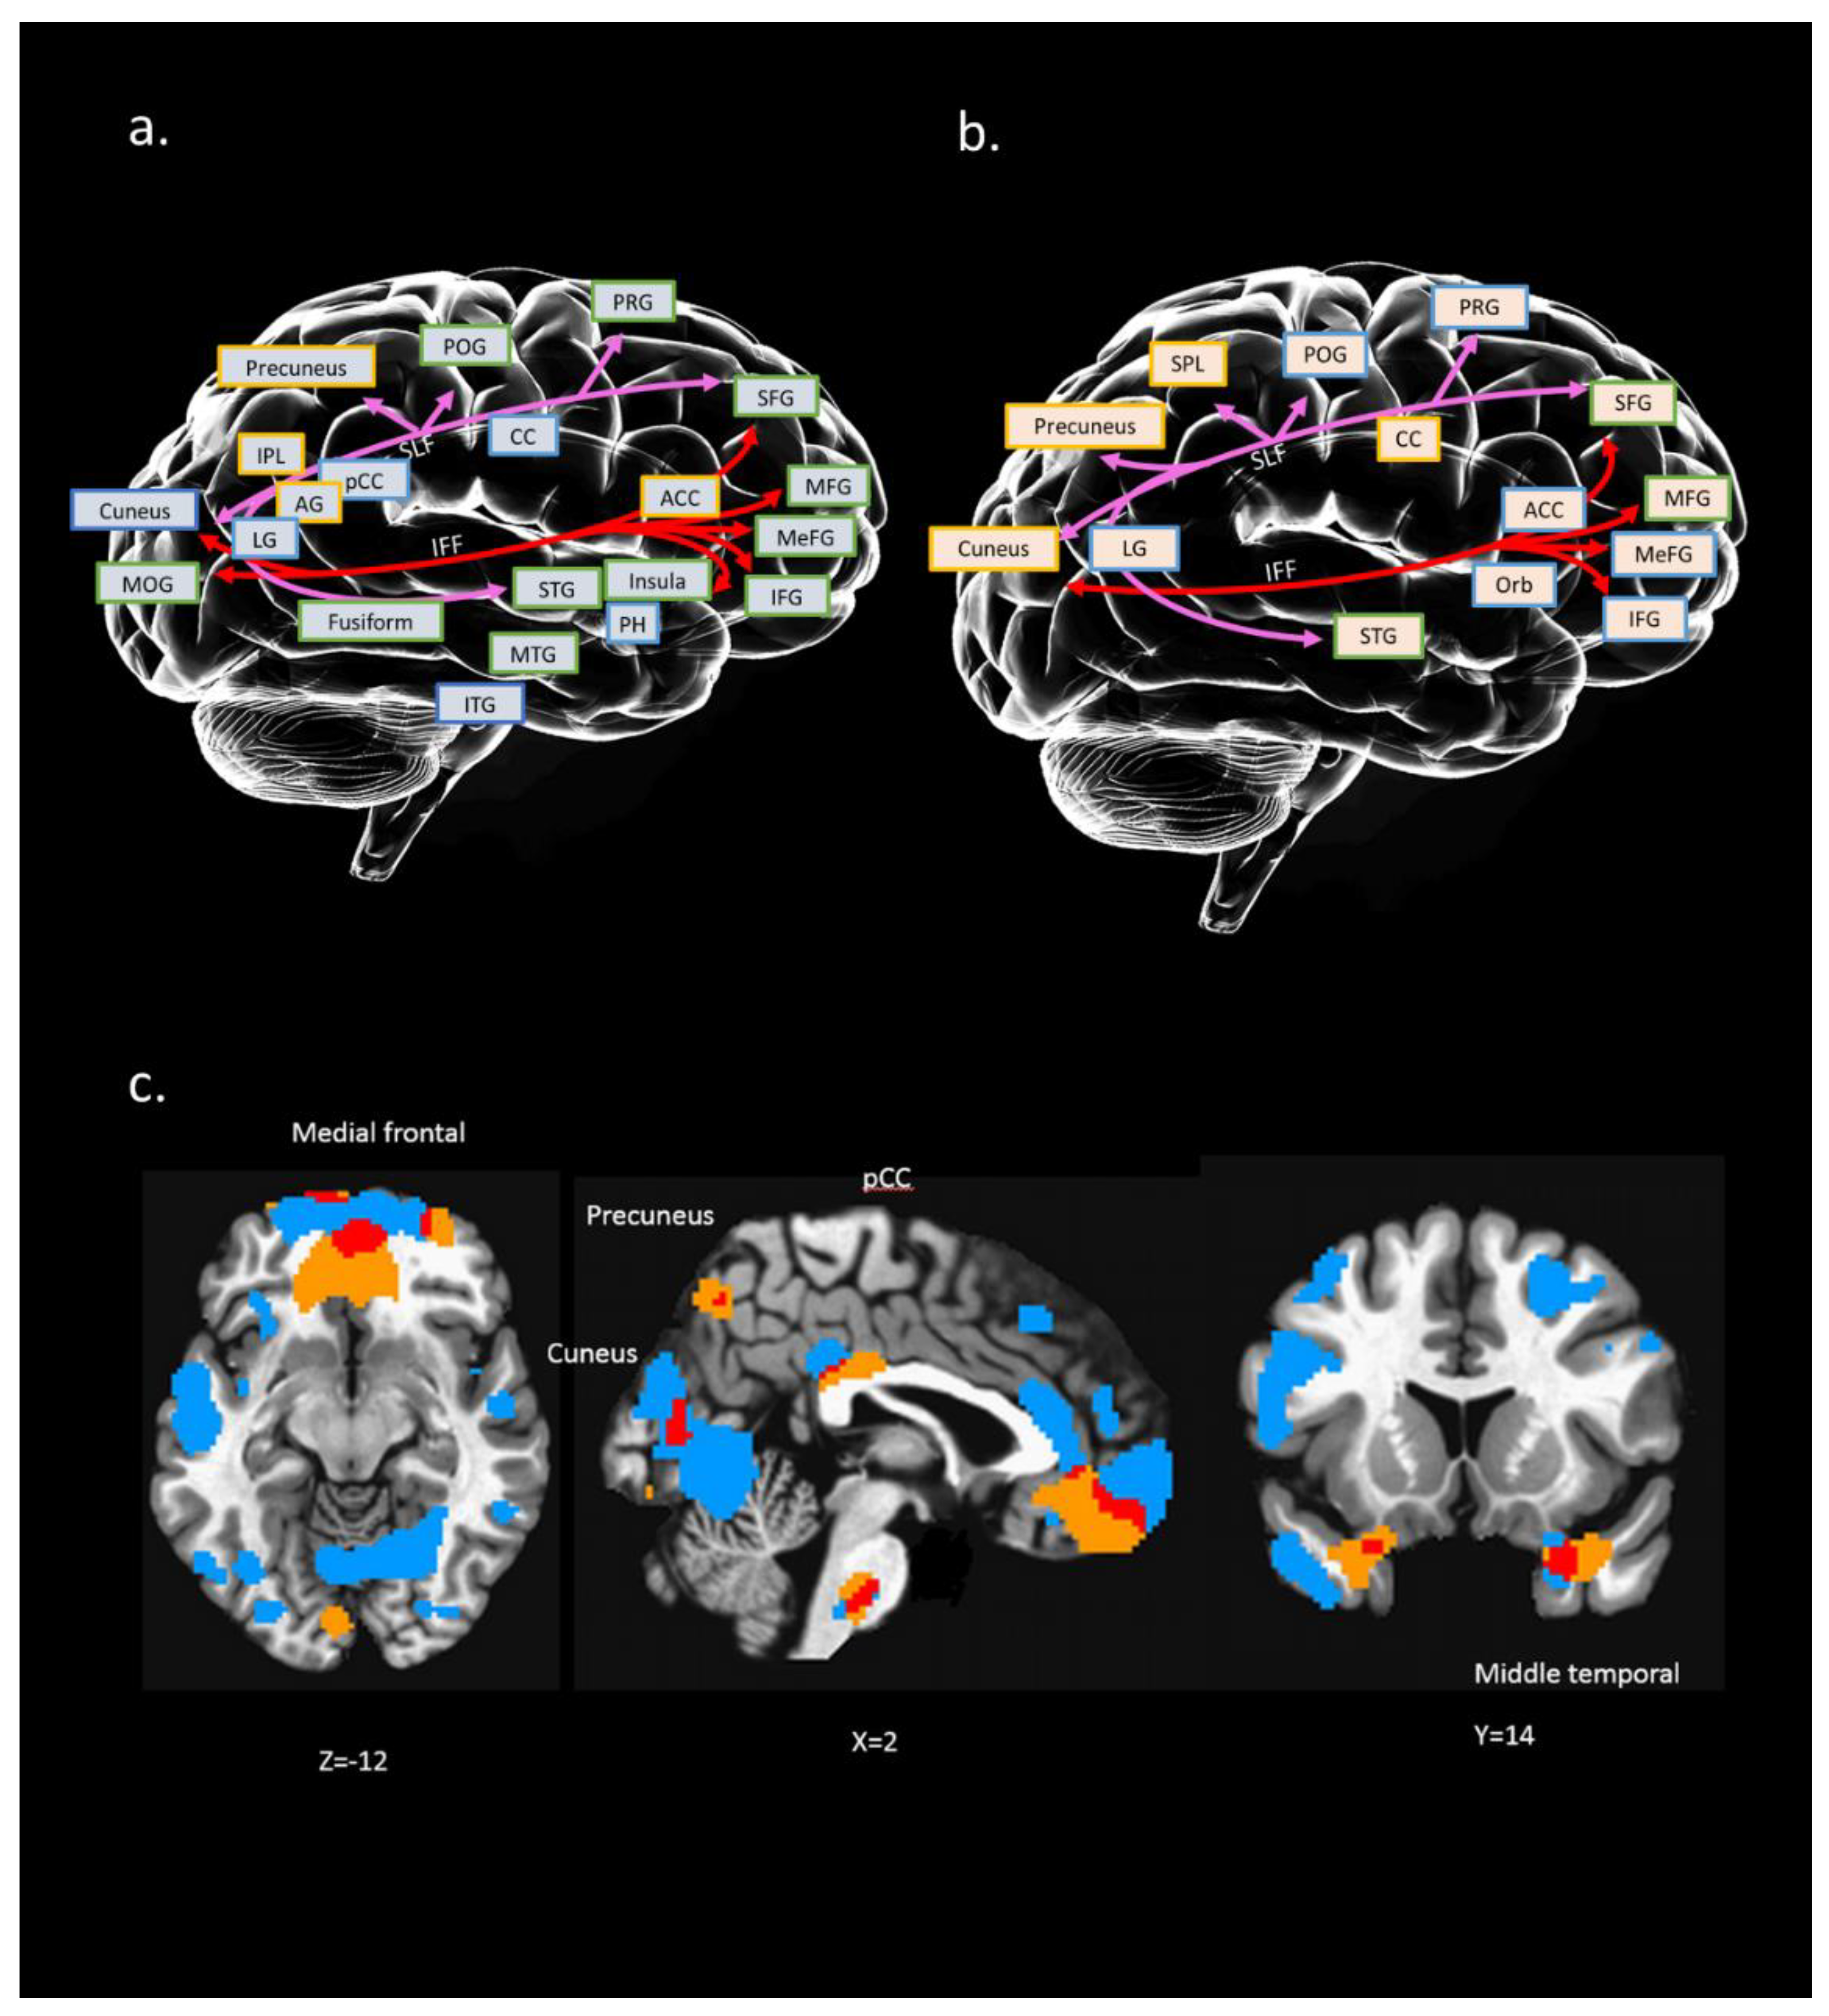

4.3. IC#23 Different Spatial Maps Associated with Psychological Resilience (RSA_p)

4.4. Interaction of Multi Modalities Among rfMRI, sMRI, and dMRI of IC#23 and Its Association with RSA_p